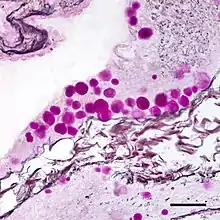

Micrograph of corpora amylacea (purple spheres) in the brain of a person with Alzheimer's disease. Combined Periodic acid-Schiff and silver stains. Bar = 50 microns (0.05 millimeters).